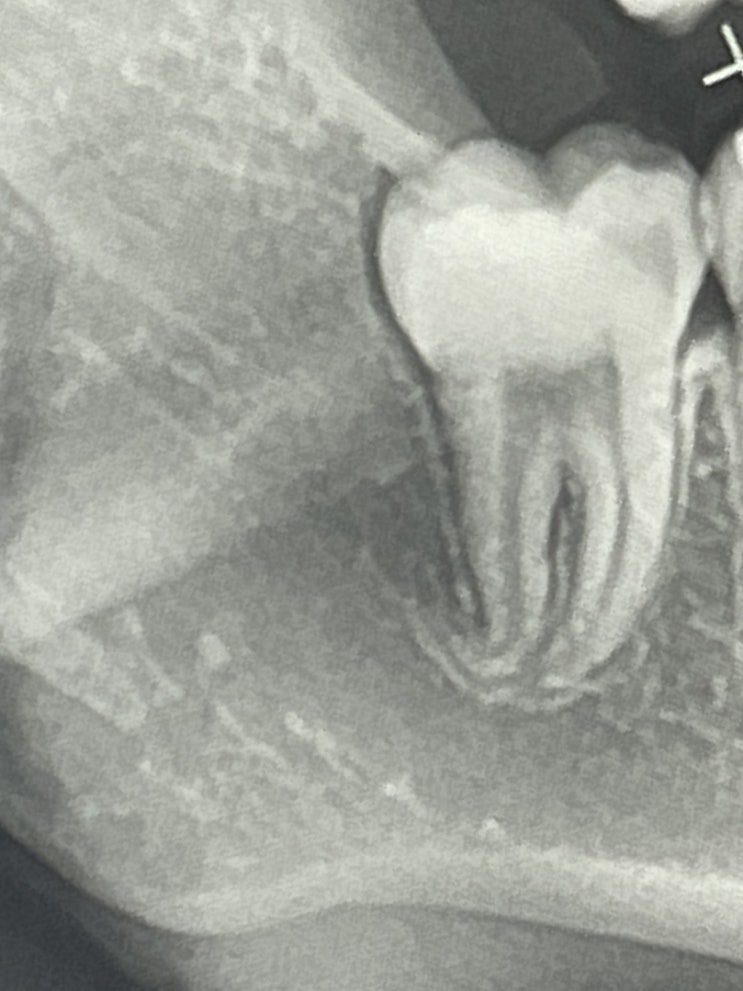

사랑니발치 후 하치조신경 마비, 안면마비

하이염,,, 23년 하반기 운이 얼마나 좋으려고 지금 액땜을 이렇게 하는 지? 23년 1월 24일 설연휴 마지...